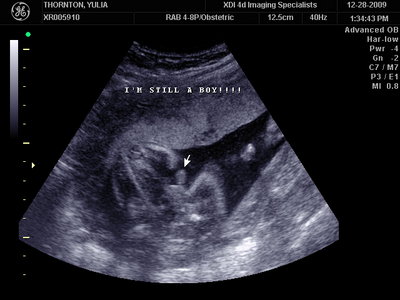

Ну ладно, тогда и я нашего писюна покажу  Надеюсь, Джеффри на меня не обидится Вот это в 23 недели: (там оборудование переключалось из режима 3Д в обычный 2Д)

MY BABY SONO!_2_15.JPG [ 112.35 КБ | Просмотров: 1171 ]

Sweetheart75 писал(а): Ну ладно, тогда и я нашего писюна покажу  Надеюсь, Джеффри на меня не обидится Вот это в 23 недели: (там оборудование переключалось из режима 3Д в обычный 2Д) Oоо, такое достоинство невозможно не заметить  А в 30 недель так вообще!